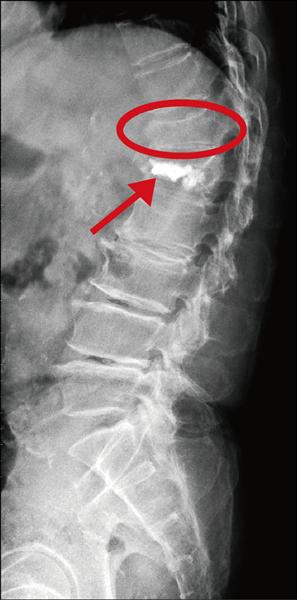

脊椎骨折別輕忽 你以為的脊椎壓迫性骨折有可能是 爆裂性骨折

脊椎骨折分類 Dr Shui